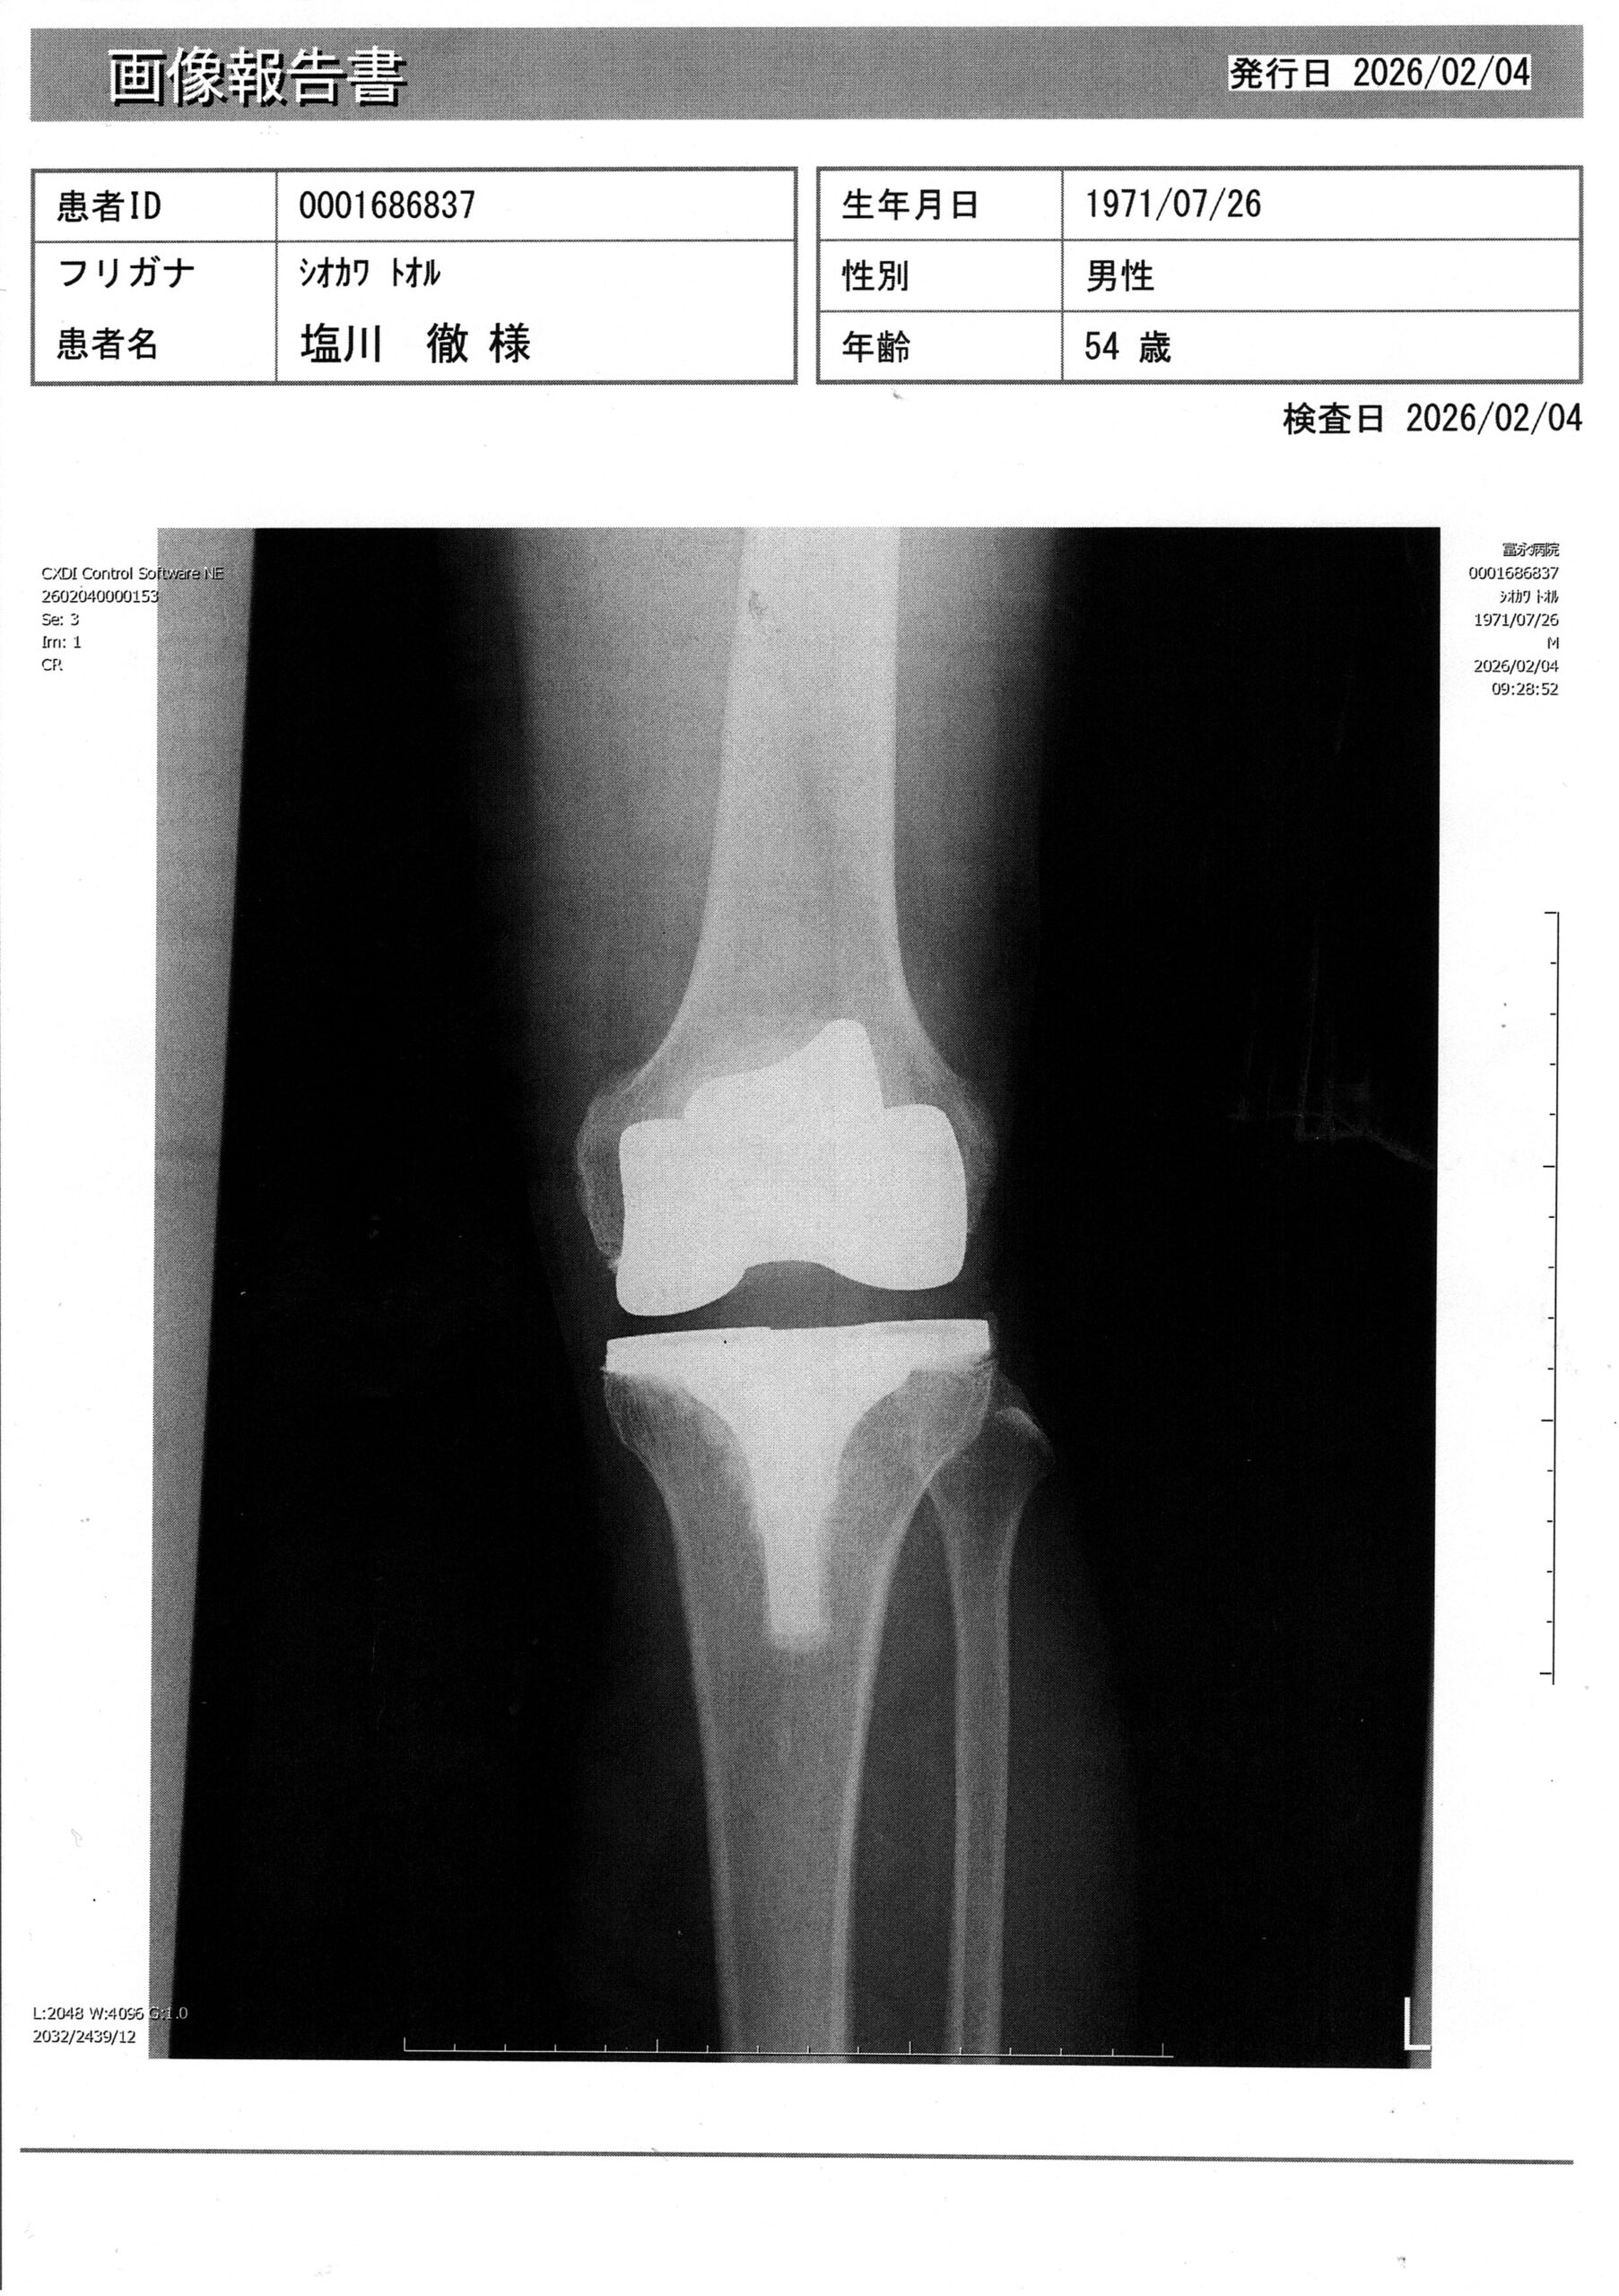

僕の左の股関節と膝関節は人工関節です。

2022年の8月に股関節を人工関節にする手術を受けまして、

2022年12月末に膝を人工関節にする手術を受けましたので、もう3年以上経つんですねぇ~

先日、病院にオペ後の定期チェックに行ってまいりました。。。

特に問題はなく、3分ほどで診察終了!!